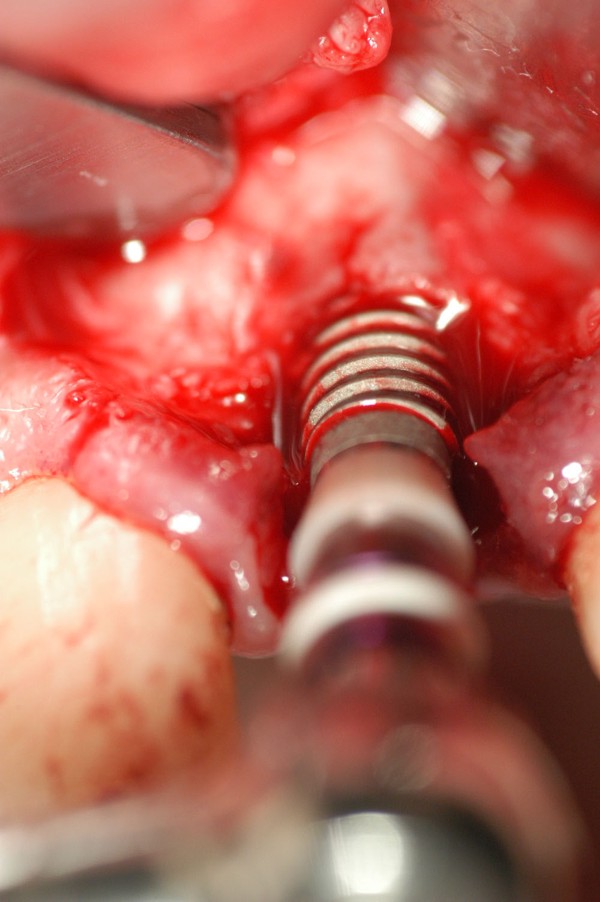

Fig.18(Pie de foto: Instalación de Implante)

Fig .19(Pie de foto: espiras al descubierto)

Fig.20(Pie de foto: Incisión del periostio)

Fig.21(Pie de foto: injerto aloplástico )

Fig.22(Pie de foto: Membrana)